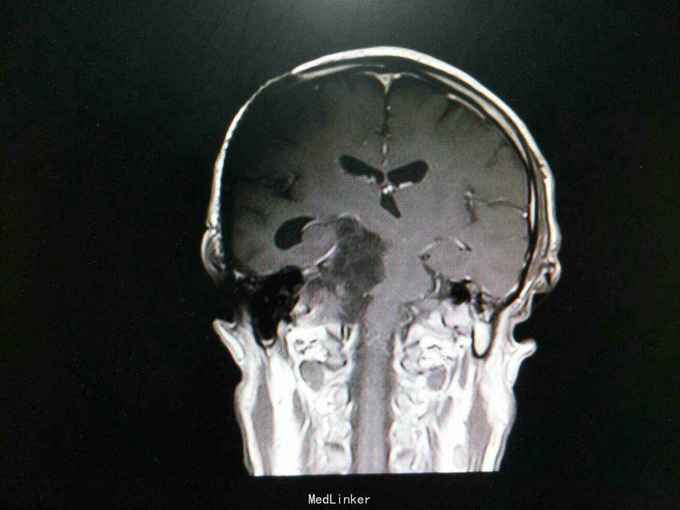

查体:生命体征平稳。神经系统检查:右侧眼睑下垂,左侧眼睑无下垂。肌力 右侧肢体肌力5-级,左侧肢体肌力正常。肌张力: 右上肢肌张力正常,右下肢肌张力正常;左上肢肌张力正常,左下肢肌张力正常。肌营养检查:四肢肌肉无萎缩。共济与平衡检查:正常。外院颅脑CT示右侧桥脑小脑角团片囊性低密度区,性质待定,蝶窦右后方局部骨质缺损代之稍低密度软组织肿块,考虑原肿瘤复发,颅骨呈术后改变,颅脑CT增强示颅内占位性病变(表皮样囊肿?)。入院后行颅脑MRI检查提示: 右侧颞骨岩尖-脚间池-右侧环池-右侧桥小脑角池见片状异常信号影,边界清,形态不规则,呈匍匐状分布,冠状位范围约47mm×29mm。相应右侧颞、脑干明显受压,脑干向左移位。第三脑室略向左移位。右侧额骨、颞骨骨皮质欠连续,呈术后改变。 考虑右侧颞骨岩尖-脚间池-右侧环池-右侧桥小脑角池表皮样囊肿。 右侧颅骨呈术后改变。